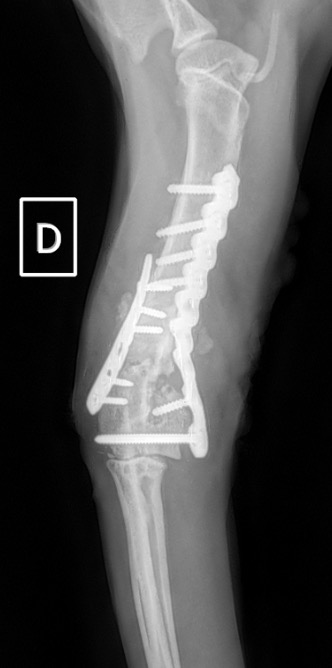

Figure 5 : Post-Op Immédiat

Notre préférence va vers le placement de deux plaques humérales : une médiale de la plus grande taille possible et l’autre latérale, généralement d’une taille inférieure à la première. Dans l’exemple 1 (chat européen), une plaque de 2 mm est utilisée médialement et une plaque de 1,5 mm latéralement. Dans l’exemple 2 (chien Malinois), une plaque de 3,5 mm est utilisée médialement et une plaque de 2,7 mm latéralement.